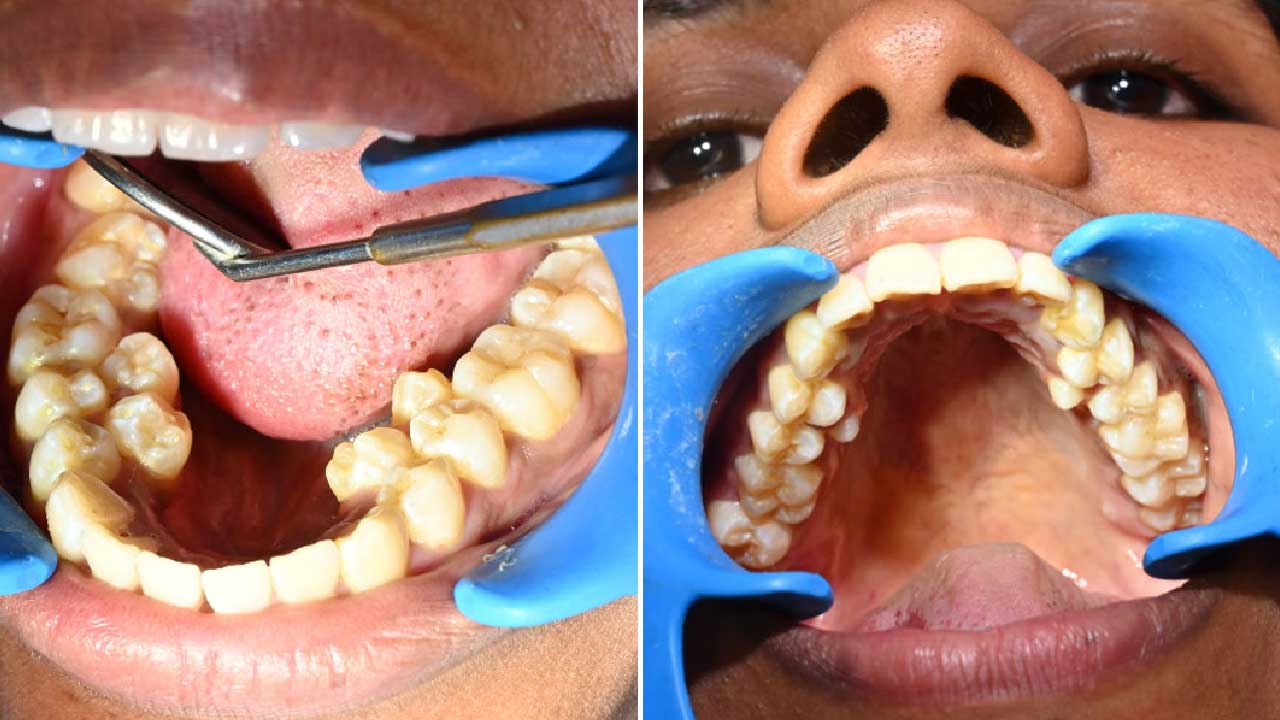

A unique world record has been set in India. A 26-year-old woman, Kalpana Balan, has a total of 38 teeth in her mouth—six more than the average person. Due to this rare condition, her name has been recorded in the Guinness World Records. This raises an important question: if someone has extra teeth, should they be removed or left as they are?

Typically, an adult has 32 teeth. However, Kalpana Balan has 4 extra teeth in the lower jaw and 2 in the upper jaw. These extra teeth began appearing gradually during her teenage years. While she does not experience significant pain, food often gets stuck between her teeth while eating.

This condition is known as Hyperdontia or supernumerary teeth, where more teeth develop than usual. It is observed in about 3–4% of the global population.